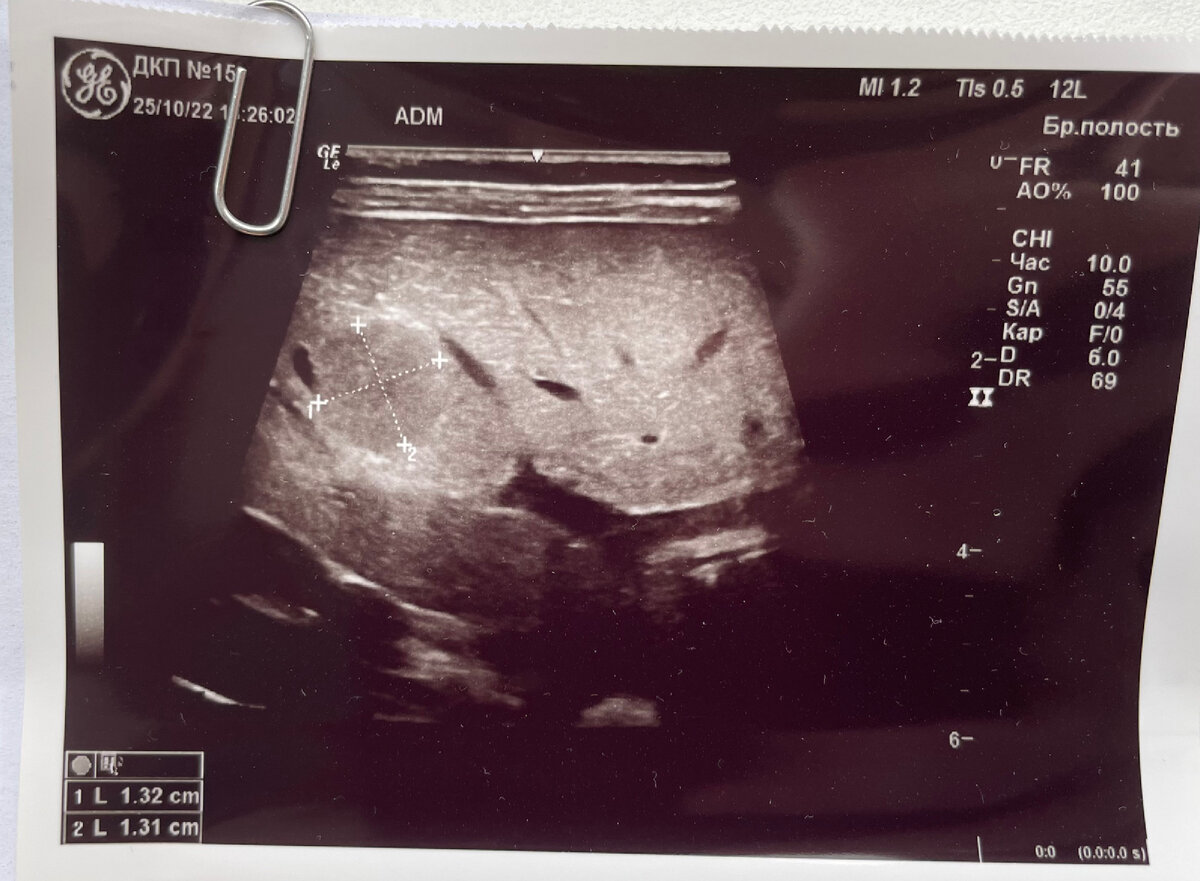

Тот самый снимок узи

А вот в печени узистка обнаружила новообразование… По протоколу нужно было снова мчаться к своему педиатру, чтобы та дала направление в онкоцентр для дальнейших обследований. Что тут скажешь, только мы пережили ковид и диагноз «можно думать о воспалении легких», так тут новая напасть!

В больнице меня успокоили, что онкомаркеры в крови - в пределах верхней нормы, а узи показало, что образование не снабжается кровяными сосудами, а значит пока не понятно что это такое… Было решено пока просто отложить прививки и сделать повторные анализы через месяц.

Новые анализы показали, что значение онкомаркера снизилось, а образование в печени стало меньше! Это были очень хорошие новости, просто камень с груди упал! Нужно было просто наблюдать и каждый месяц приезжать сдавать анализы.

Так мы проездили полгода. Каждый раз значения онкомаркера уменьшаличь, а образование становилось всё меньше, пока совсем не исчезло! На последнем визите врач разрешил возобновить прививки (календарь сдвинулся больше, чем на полгода) и на профилактическое обследование приехать через 6-12 месяцев!